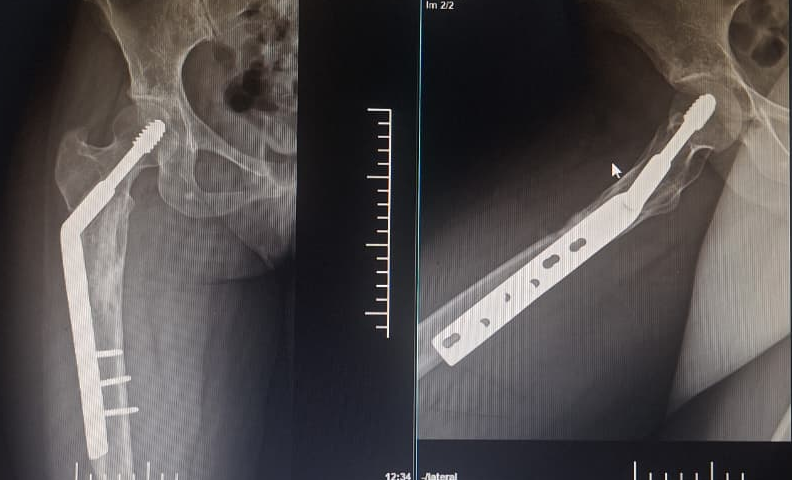

In 2022, the patient presented with progressive pain and restricted range of motion of the right hip following minor trauma. She was re-evaluated clinically and imaging was done. Radiographs (Fig 4 ) and MRI (Fig 5) revealed an expansile lytic lesion of the right proximal femur consistent with intraosseous hemangioma. Due to risk of pathological fracture we planned for fixation of right proximal femur. She underwent right proximal femoral bone excision biopsy and dynamic hip screw fixation with iliac–fibular strut bone grafting (Fig 6). Post-operative period was uneventful. Started partial weight bearing after 45 days followed by full weight bearing by 90 days. Very good radiological incorporation of graft noted and fixation was stable radiologically (Fig 7). Histopathology report suggestive of benign bone hemangiomatous tissue without any features of malignancy (Fig 8).

• Postoperative consolidation of proximal femoral graft (Fig 7).

Intervention

The patient underwent right proximal femur bone excision biopsy, dynamic hip screw fixation, and iliac–fibular strut bone grafting to prevent structural collapse and improve mechanical stability (Fig 6). Post-operative imaging confirmed adequate consolidation over 3 year follow-up period (Fig 10).